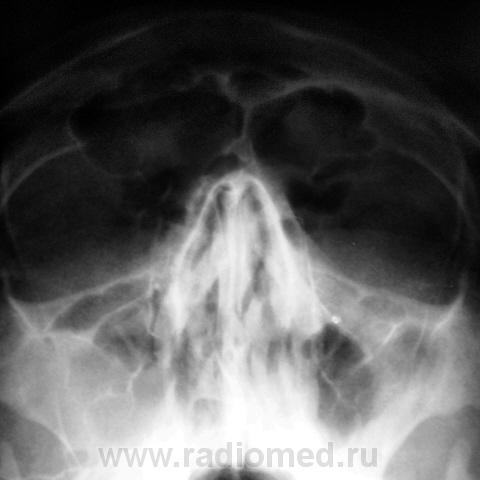

Направлен на рентгенографию придаточных полостей носа.

а мне кажется не норма, правая верхнечелюстная пазуха наполовину затенена, да и влевой по медиальной стенке какой то выбухающий контур и вроде фиброзные наслоения есть. Наш отоларинголог полечил бы, а потом к нам на контроль.

Хронический гиперпластический двусторонний гайморит, обострение справа(выпот)

Пациент находится в областной больнице, в оториноларингологическом отделении, прооперирован. Что конкретно? Буду знать, когда пациент вернется по месту жительства.

Мне все ясно, так бы сразу и сказали: есть клиника. Надеюсь не радикальную сделали? Полипы-то есть? Эта информация должна быть у ЛОРа и до операции.

Пациент направлен отоларингологом на рентгенографию придаточных полостей носа.